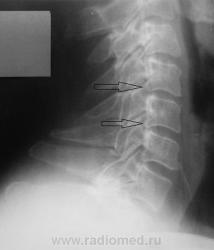

Уважаемые коллеги! Данные снимки произведены вне какой-либо связи с травмой или жалобами на боли. Просто такая картинка встречается довольно часто. Как Вы для себя интерпретируете такие деформации задних углов тел позвонков? Могут ли они вызывать неврологические жалобы? Является ли это следствием остеохондроза? На мой взгляд, на краевые костные разрастания в обычном их понимании это мало похоже.

На рентгенограммах шейного отдела позвоночника в 2-х проекциях определяется сглаженность физиологического лордоза,  снижение высоты межпозвонковых дисков на уровне С4-5 2 ст., С5-6 1 ст., уплотнение замыкательных пластинок, скошенность передневерхних углов С3-7, деформация тела С4, передние осеофиты тел С4-С6, задние С5-6, остеофиты унковертебральных сочленений. Явления субхондрального склероза межпозвоночных суставов.

Заключение: Остеохондроз шейноо отдела позвоночника 2 ст. Спондилоартроз.

Вполне согласен. Стрелки указывают на вариант формы. Хотя есть выпрямленность лордоза, и в дугоотросчатых суставах тоже нужно посмотреть. Но ведь за это нас не спрашивают.

Деформация задних углов тел-есть НЕПОСРЕДСТВЕННЫЙ признак Деформирующего спондилеза(значит,рядом остеохонроз и,вероятно,спондилоартроз),который вызывает проявления радикулярной симптоматики(там рядышком  с задними отделами тел корешки нервов выходят-авт.),и как следствие сего-выпрямление шейного лордоза для "декомпрессии" тех же самых нервов...Вспомните дедушек,которые при одностороннем радикулите на прямом снимке "дают" наклон в здоровую сторону!Здесь та же ситуация, только в сагитальной плоскости.

Норма.Вариант строения лимба тел позвонков.Выпрямленность лордоза может быть следствием укладки. Диаметр корешка и диаметр спинно-мозгового отверстия в шейном отделе позвоночника соотносяться как 1:16 , если не ошибаюсь, т.е. 16-кратный запас прочности, для компенсации заложен природой в случае подобных конфликтов(компрессия корешка).Корешковые синдромы на шейном уровне редкость.Тем более клиники нет. О чём вести речь.Скверно,коллеги, когда мы свои умозрительные представления искренне подаём как истину.